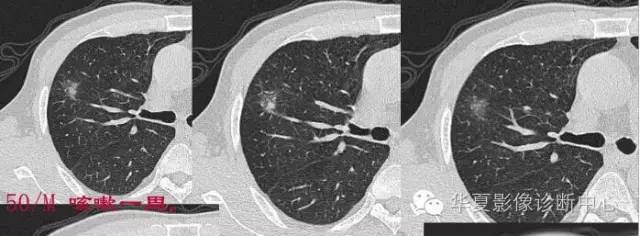

第一步判断是不是肿瘤

孤立性GGO

首先看边缘

是否清楚

GGO的边缘模糊,考虑炎性病变